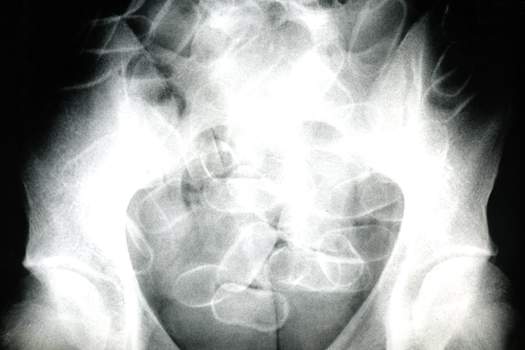

Am Anfang ist es nur eine Vermutung